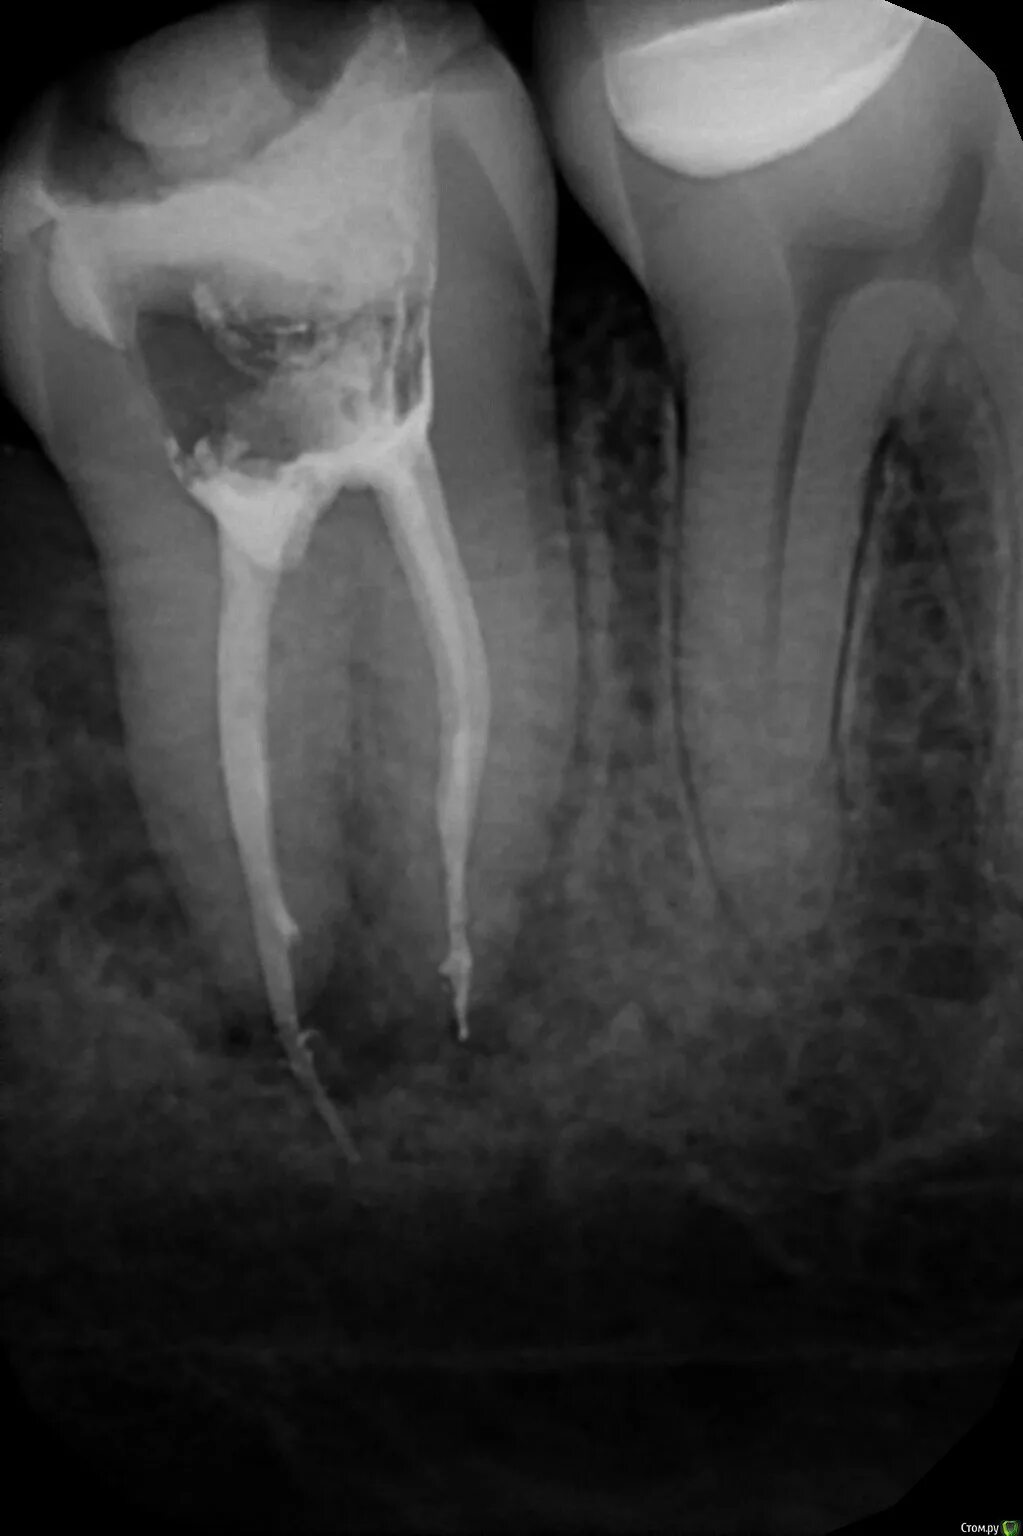

Удалить нервы запломбировать